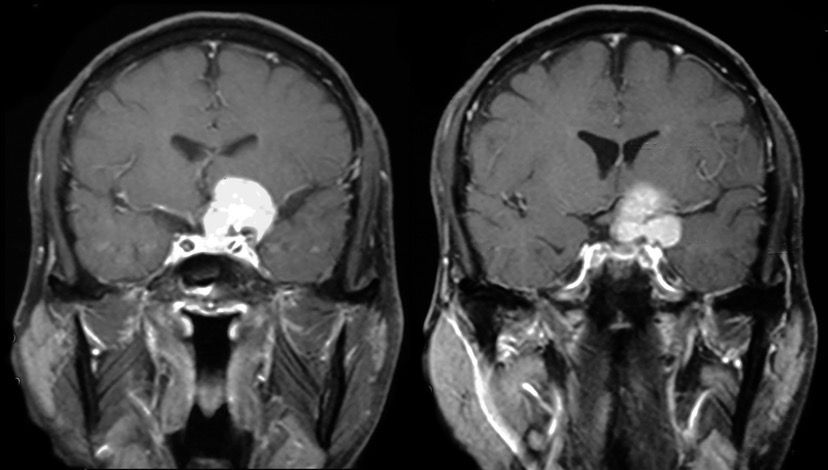

病例2:男性,55岁,因左眼视力进行性下降1年余入院。

查体:神清,对答可,粗测左眼视力全盲,右眼 0.8 ,左瞳2.5mm,直接对光反射消失,间接对光反射存在,右瞳直接对光反射存在,间接对光反射消失,眼球各方向活动正常,四肢肌力正常,深浅感觉正常,病理征(-)。

MRI检查:

CTA血管造影及三维重建: